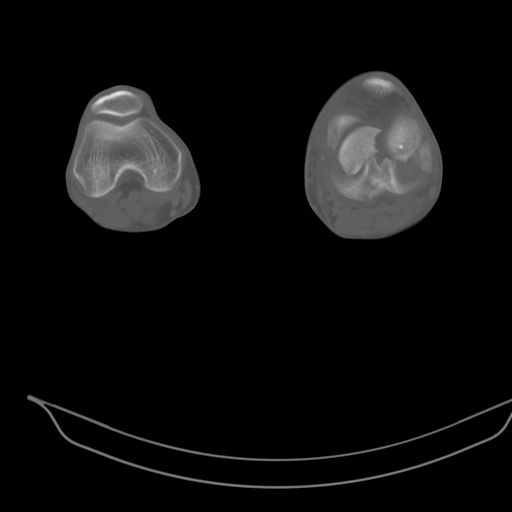

This is a coronal split in the femoral condyle and is a rare injury. Please see attachment for ORIF result

При внутрисуcтавных переломах трехмерные (3D) изображения, кроме красивого снимка, не дают полную информацию о состоянии отломков, самыми информативными являются корональные срезы на КТ и обычная длинная ренгенограмма конечности для сравнения оси конечности.

Фронтальные внутрисуставные переломы мыщельков бедра, так называемые Hoffa fracture, не частые, но встречающиеся переломы, в основном они связаны с травмой высокой энергией.

В зависимости от смещения рекомендуется сопоставление костных фрагментов с последующей жесткой фиксацией.

В вашем случае доступ будет медиальный, сопоставить развернутый медиальный мыщелок и фиксацию надо произвести в передне-заднем

направлении шурупами 4.5 мм в диаметре, углубив головку шурупов под хрящ, а поперечную фиксацию - межмыщелковыми шурупами. Желательно применить шурупы 6.3 мм в диаметре. Дополнительная Buttress technique пластина предотвратит перелом от скольжения.